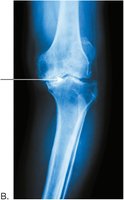

Synovial joints: Freely moveable, include hinge (elbow, knee) and ball-and-socket (shoulder, hip)

Osteoarthritis is a degenerative joint disease characterized by the breakdown of articular cartilage and narrowing of joint space.

Symptoms include pain, stiffness, and reduced mobility.

Fracture Management

Fractures are treated with immobilization (casts, splints), reduction (realignment), and sometimes surgery.

Internal Fixation

Severe fractures may require internal fixation with plates and screws to stabilize bone fragments during healing.